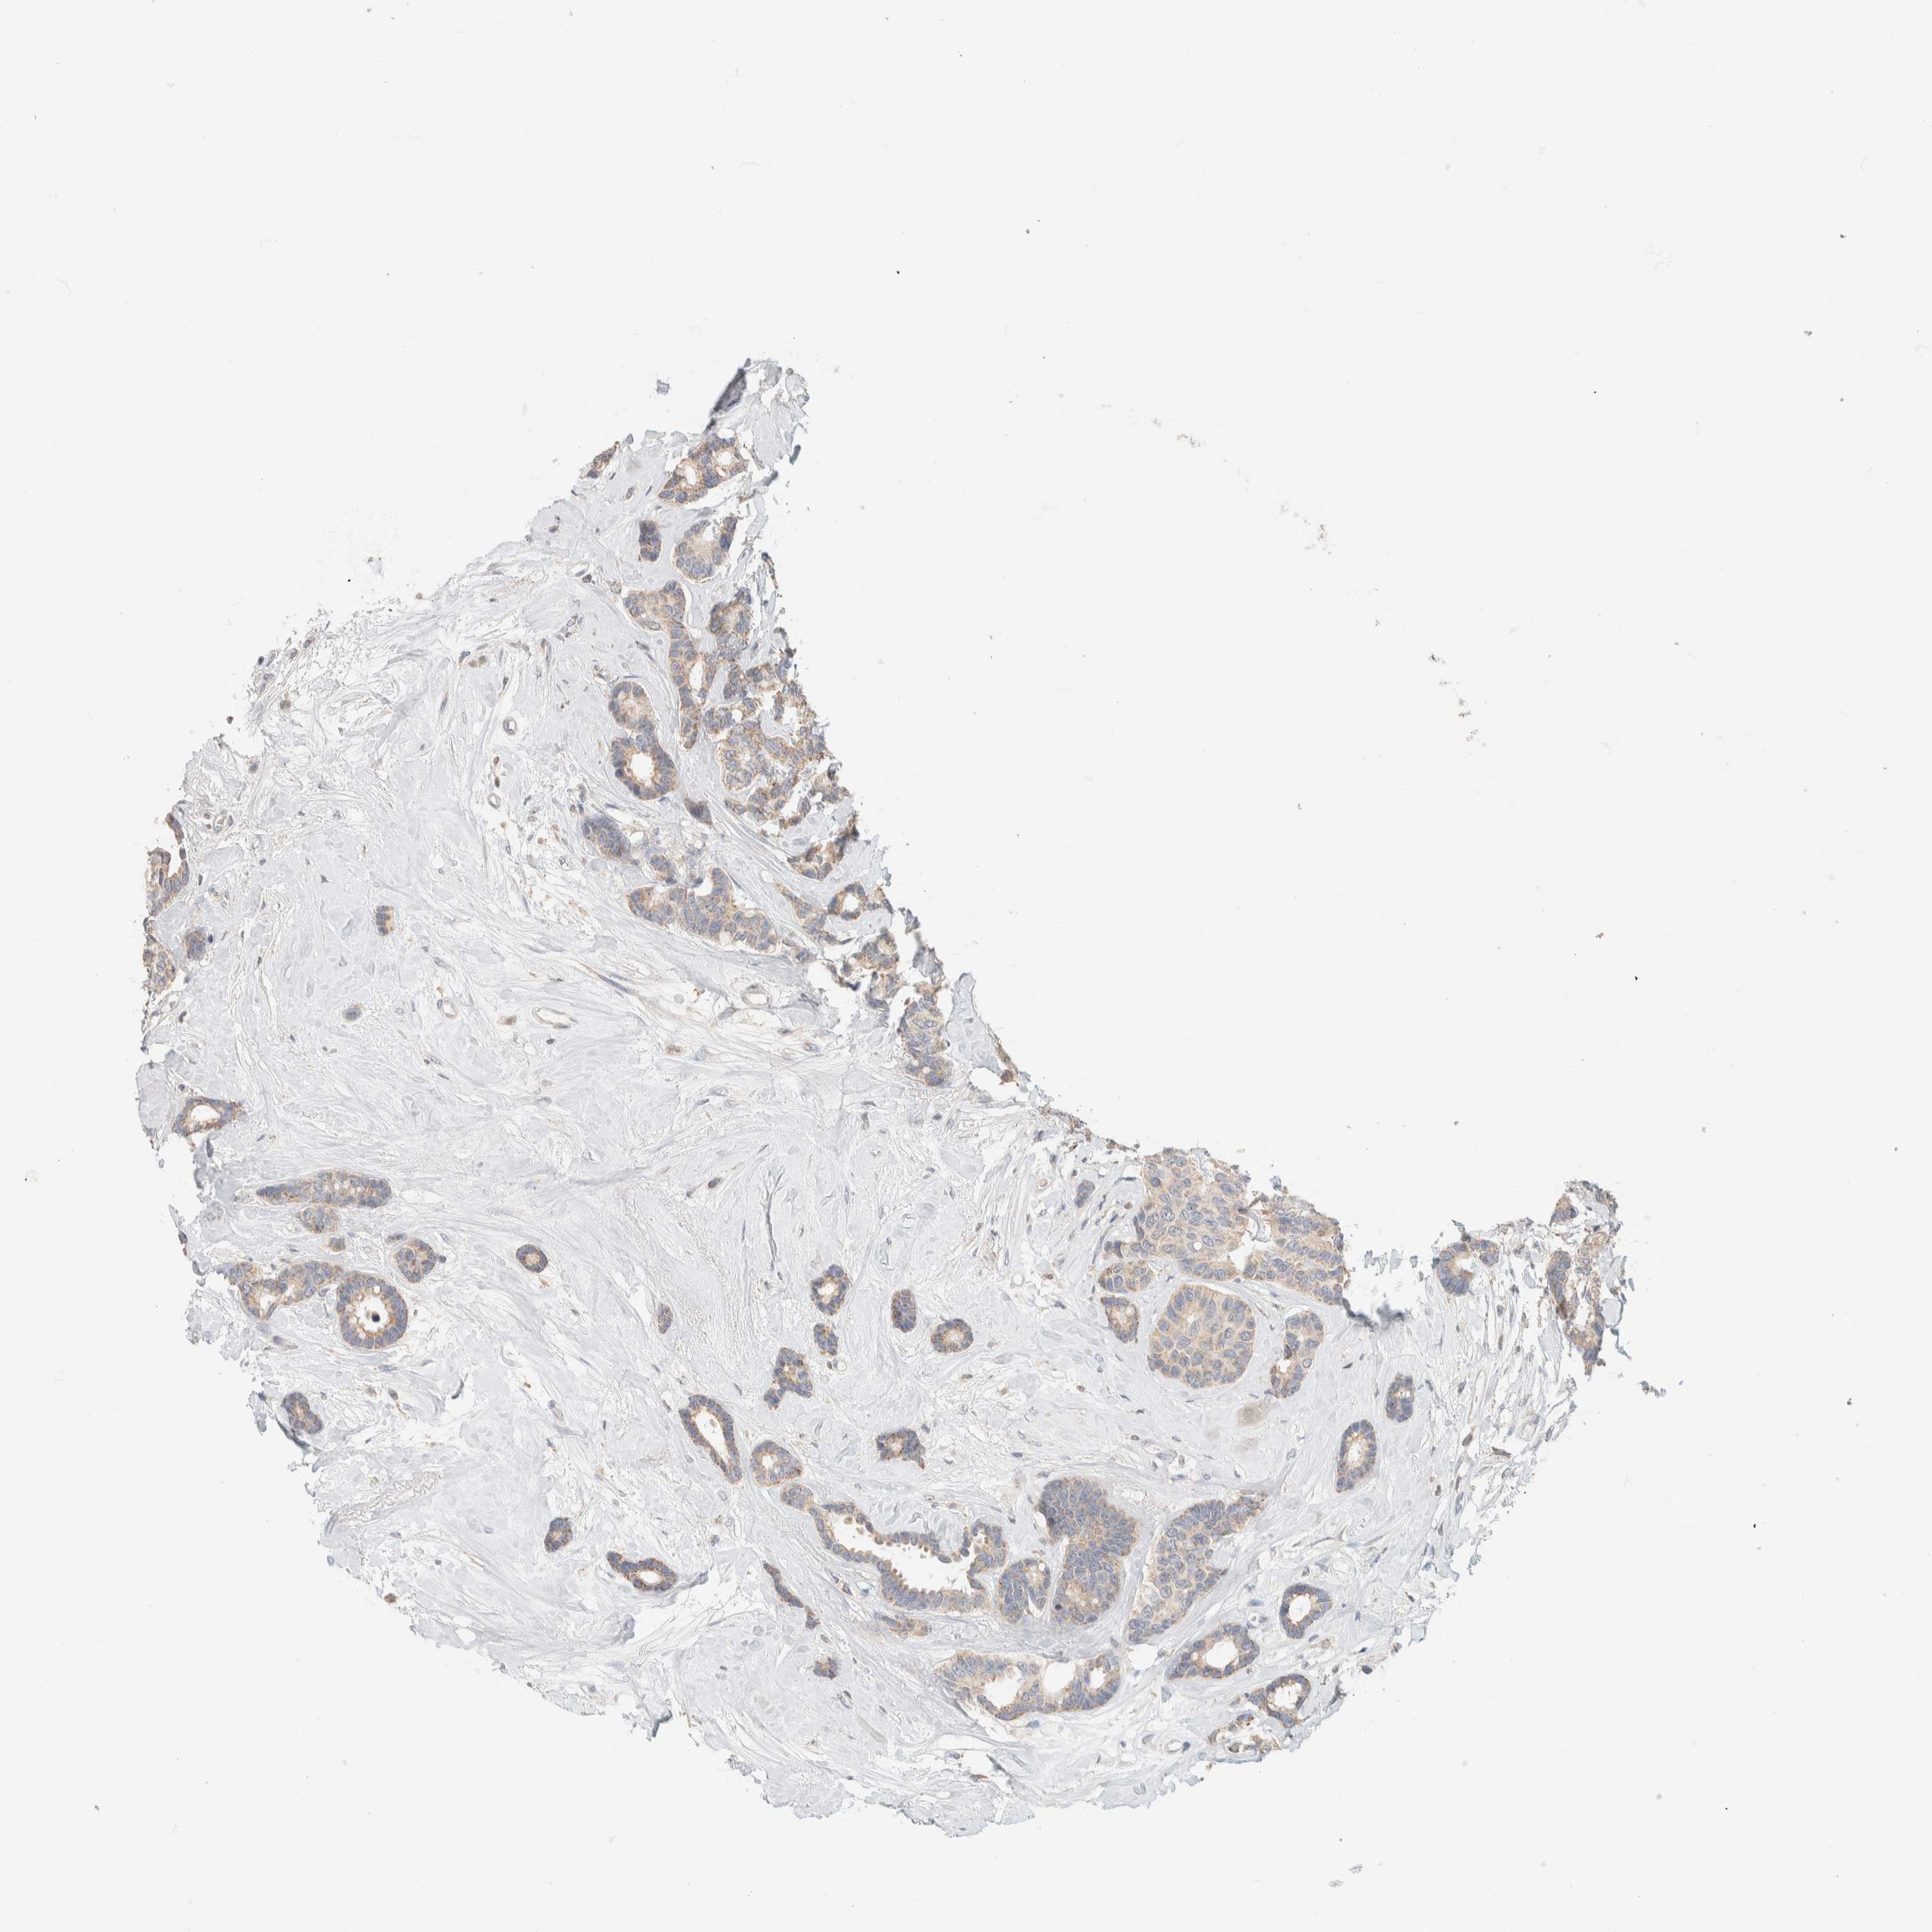

CANCER BREAST CANCER Show tissue menu

BRCA TCGA BRCA VALIDATION PROTEIN EXPRESSION